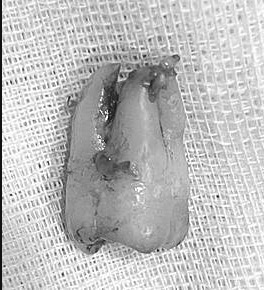

拔牙案例

智齒牙根彎曲怎麼拔?

拔牙過程中醫師會分段截斷牙齒,或者視情況修磨周圍骨頭,拔牙也講求「適度力量」,避免傷及鄰牙或牙根斷裂。

18-25歲的年紀骨質較軟,拔牙會較順利

傷口復原也會比較快呦!